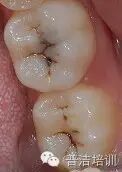

临床检查:36 37牙合面发育沟内探及龋损,探诊(—),叩(-),冷热诊无不适

诊断:36 37中龋

治疗设计:因36 37牙合面形态完整,故选用印章法树脂充填。

初始片